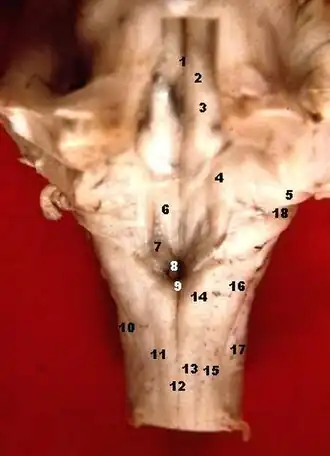

![]() Dorsal cochlear nucleus is #4, at upper left | |

Human caudal brainstem posterior view (Dorsal cochlear nucleus is #5) | |